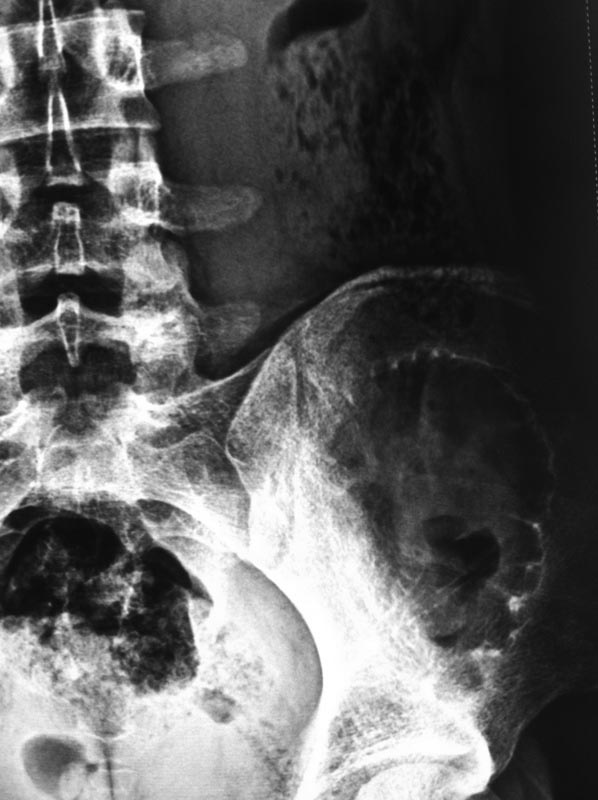

Несмотря на кажущуюся легкость, установить правильный диагноз кисты подвздошной кости бывает сложно. Во-первых, из-за локализации, потому что излюбленным местом костной кисты является проксимальный отдел бедра или плеча, а в тазу киста встречается редко. Еще из-за рентген схожести, кисту ошибочно путают с фиброзной дисплазией, сосудистой кистой или вообще неоплазмой!

Правильный диагноз устанавливается на основании комбинированных исследований: КТ, МРТ, рентген и биопсии. Содержимое кисты обычно чистая серозно-кровянистая жидкость и стенка - реактивная фиброзная мембрана.

Большинство костных кист таза обнаруживается при тазовых исследованиях случайно. А перелом тонких стенок срастается быстро и бессимптомно, но на рентгене остаются дополнительные тени, которые ошибочно принимают за фиброзную дисплазию.

Подвздошная кость в нагрузке не участвует, и при отсутствии клинических симптомов не требуется лечение. Симптоматические можно лечить декомпрессией биопсионной иглой или сверлением.